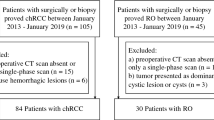

Our institution’s radiography and pathology databases were searched between June 2013 and January 2021 to identify all RO, ccRCC, chRCC, and pRCC cases. Two radiologists with four and six years of professional experience reviewed these patients. The identified cases were evaluated according to the inclusion criteria listed below: (a) All patients received a four-phase CT scan that included a preoperative CMP, nephrographic phase (NP), EP, and pre-contrast phase. The EP images were collected more than 20 min after the contrast injection. (b) All of the cases were histologically identified after partial or radical nephrectomy. (c) All patients were evaluated to ensure that only tumors visibly displaying stellate or irregular CHA in CMP imaging were included in the study. Eventually, the final initial dataset included 132 tumors from 132 patients, of which 23 were ROs, 85 were ccRCCs, 18 were chRCCs and 6 were pRCCs. Ultimately, the study population comprised 70 men and 62 women; the mean age ± standard deviations (SDs) were 58.1 ± 10.5 years. The participants were separated into three groups: RO (n = 23), ccRCC (n = 85), and non-ccRCC (n = 24).

Subsequently, we included a validation dataset to validate the final prediction models that included CHA features. All of the validation dataset’s samples were collected from a single institution throughout the same time frame and using the same inclusion criteria as the original dataset. The validation dataset comprised 28 men and 25 women; the mean age ± SDs were 57.1 ± 10.1 years. They were also separated into three groups: RO (n = 8), ccRCC (n = 35), and non-ccRCC (n = 10). Among them, the non-ccRCC group included 8 chRCCs and 2 pRCCs.